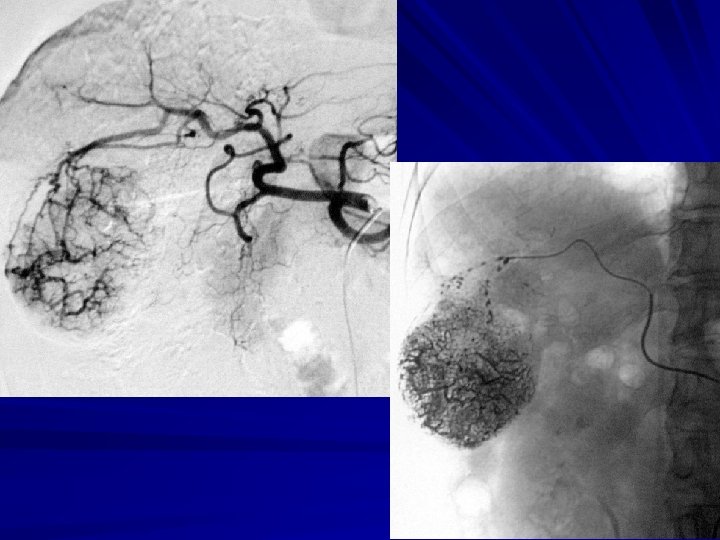

Use of microcatheter— OAs TACE

Use of microcatheter —KUB after OAs TACE

RESULT-2 97 parasitic OA branch were found in 32 patients. 6 patients were found OA supplying at the first TACE procedure. 62 OA branches with microcatheter were performed superselective TACE, successful rate was 63. 9%(62/97).

RESULT-4 Angiography characteristics : (1) hypertrophy of the feeding OAs were noted in 28 patients (n=28) ; (2) OAs’ edges are untidily and rigidity (n=11) , huge HCC compressed gastroduodenal artery and it’s branches displaced were noted ; (3) defective tumor staining or defective lipiodol deposit in 7 patients (n=7).